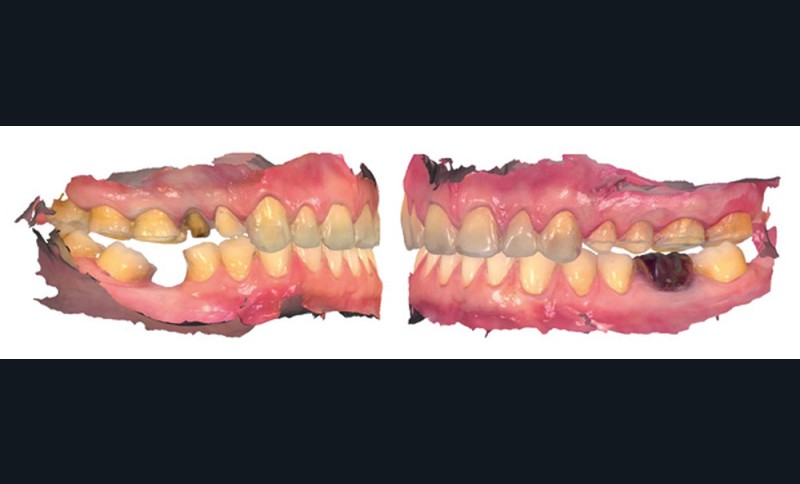

Mme V. est adressée au cabinet dentaire pour une réhabilitation de son sourire. À l’examen clinique, elle présente des usures sur l’ensemble de son maxillaire (fig. 17 et 18). Après évaluation du décalage OIM-ORC, une position de référence en relation centrée avec une dimension verticale augmentée est enregistrée. Pour valider cette position, il est demandé au laboratoire de réaliser un wax-up virtuel. Ce dernier est validé puis transféré en bouche pour essayage (fig. 19 et 20).

Ce mock-up est équilibré puis transformé en projet provisoire pour trois mois afin de s’assurer de la stabilité, du confort masticatoire et de l’esthétique. Au terme de ces trois mois, une empreinte de la situation est réalisée ainsi que l’enregistrement de l’occlusion ; enfin les secteurs postérieurs sont préparés pour recevoir des overlays. L’ensemble des informations (position et forme) est repris au sein du laboratoire pour dessiner les prothèses d’usage. Ces dernières seront produites par usinage, puis maquillées avant d’être envoyées au cabinet pour assemblage par collage sous champ opératoire (fig. 21 à 23).

Une fois les secteurs postérieurs et l’assise occlusale rétablis, le bloc incisivo-canin antérieur est préparé pour des restaurations adhésives. Là encore, l’assemblage se fait par collage sous champ opératoire. Le suivi est assuré pour contrôler la pérennité du traitement et une éventuelle reprise des usures. Pour ce faire, des rendez-vous cliniques avec réalisation d’une empreinte optique semestrielle sont programmés. La précision de l’empreinte permet ainsi de dépister le moindre phénomène d’usure (fig. 24 à 27).